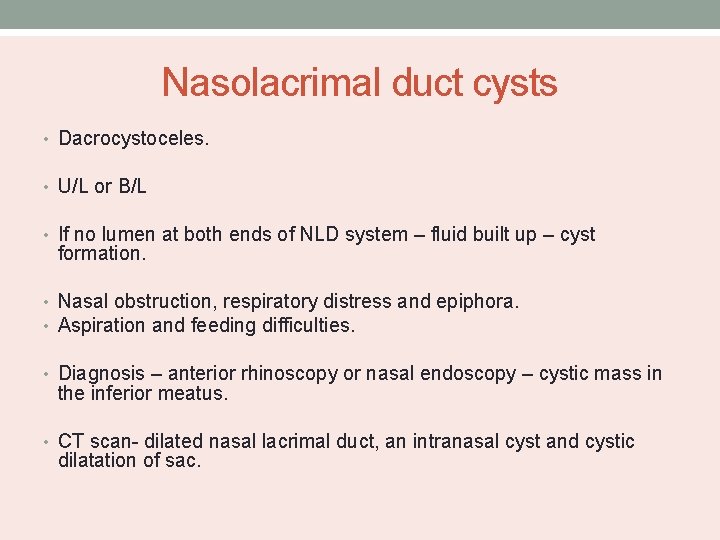

Nasolacrimal duct cysts • Dacrocystoceles. • U/L or B/L • If no lumen at both ends of NLD system – fluid built up – cyst formation. • Nasal obstruction, respiratory distress and epiphora. • Aspiration and feeding difficulties. • Diagnosis – anterior rhinoscopy or nasal endoscopy – cystic mass in the inferior meatus. • CT scan- dilated nasal lacrimal duct, an intranasal cyst and cystic dilatation of sac.

Management • Cyst is marsupalized endoscopically into the inferior meatus. • Lesion is opened with curette or microsurgical debrider.